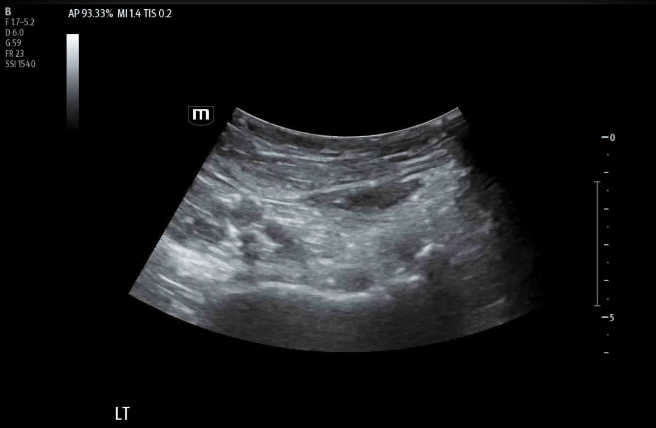

• A 20+ gauge long spinal need will be used in a lateral-to-medial approach until the needle comes in contact with the ilium. This procedure is done with in line technique.

• Target is the subfascial plane underneath the psoas tendon/above the ilium.

• It is important to visualize the needle tip during the procedure.

• Remember the probe is already in the ideal position with all the landmarks identified, so the needle will have to be corrected with micromovements to stay in the window of the probe.

Inserting needle towards the psoas tendon.